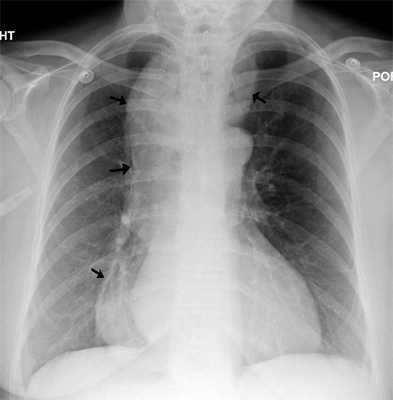

На обзорной рентгенограмме грудной и брюшной полости заметно расширение средостения и горизонтальный уровень жидкости с воздухом в пищеводе. В желудке газовый пузырь отсутствует.

При рентгеноконтрастном исследовании бариевая взвесь задерживается над суженной кардией, создавая картину «опрокинутого пламени свечи», «хвоста редиски», затем барий поступает в желудок. Пищевод может быть значительно расширен, иногда приобретает S-образную форму.